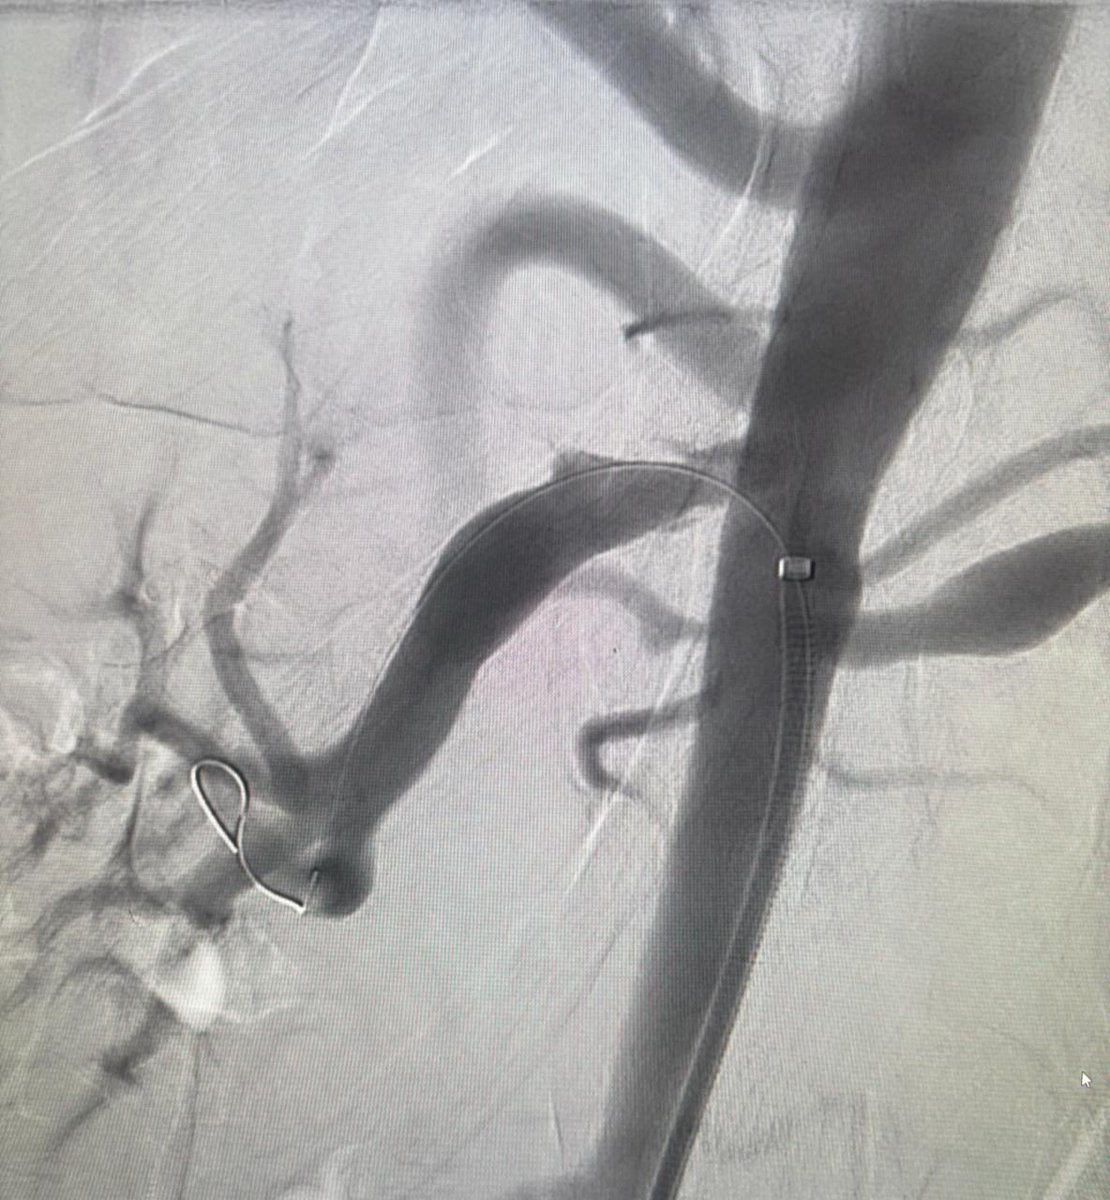

Different angiographic manifestations of four patients with retroperitoneal hemorrhage. One iatrogenic (post nephrostomy) and three spontaneous (anticoagulation). All successfully treated with embolization. Azzam Khankan عزام خانكان ghassan atassi د. عبدالقادر القناوي Majed Abdulhaq @SalmanFelemban

Different angiographic manifestations of four patients with retroperitoneal hemorrhage. One iatrogenic (post nephrostomy) and three spontaneous (anticoagulation). All successfully treated with embolization. <a href="/AzzamKhankan/">Azzam Khankan عزام خانكان</a> <a href="/AtassiGhassan/">ghassan atassi</a> <a href="/AAlkenawi/">د. عبدالقادر القناوي</a> <a href="/DrMajedAbdulhaq/">Majed Abdulhaq</a> @SalmanFelemban